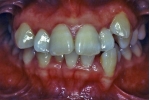

日本矯正歯科学会専門医課題症例(第3症例)

カテゴリー:Class Ⅱ division 1(抜歯症例)

大臼歯関係がclassⅡ、overjet 6mm以上、U1-SN 110度以上、ANB 6度以上が望ましいという条件は第二症例と同じ。FMAの条件がはずれた代わりに、抜歯ケースとして治療することを必須とする。

| マルチブラケット終了時